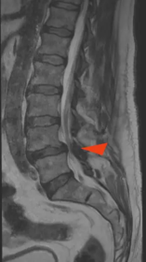

Stenosi Lombare

La stenosi spinale lombare è una condizione degenerativa in cui lo spazio disponibile per le strutture nervose e vascolari all’interno del canale spinale si riduce. Questa riduzione può portare a una compressione delle radici nervose e, nei casi sintomatici, provocare dolore o affaticamento localizzati ai glutei e/o agli arti inferiori. Tali sintomi possono essere presenti anche in assenza di mal di schiena.

Le radici nervose più frequentemente coinvolte sono, in ordine: L5, S1 e L4. Questo è coerente con l’anatomia: il forame spinale aumenta di calibro fino a L5, ma si restringe notevolmente tra L5 e S1. Inoltre, la radice di L5 ha un diametro maggiore, quindi occupa più spazio nel forame vertebrale, risultando più suscettibile alla compressione.